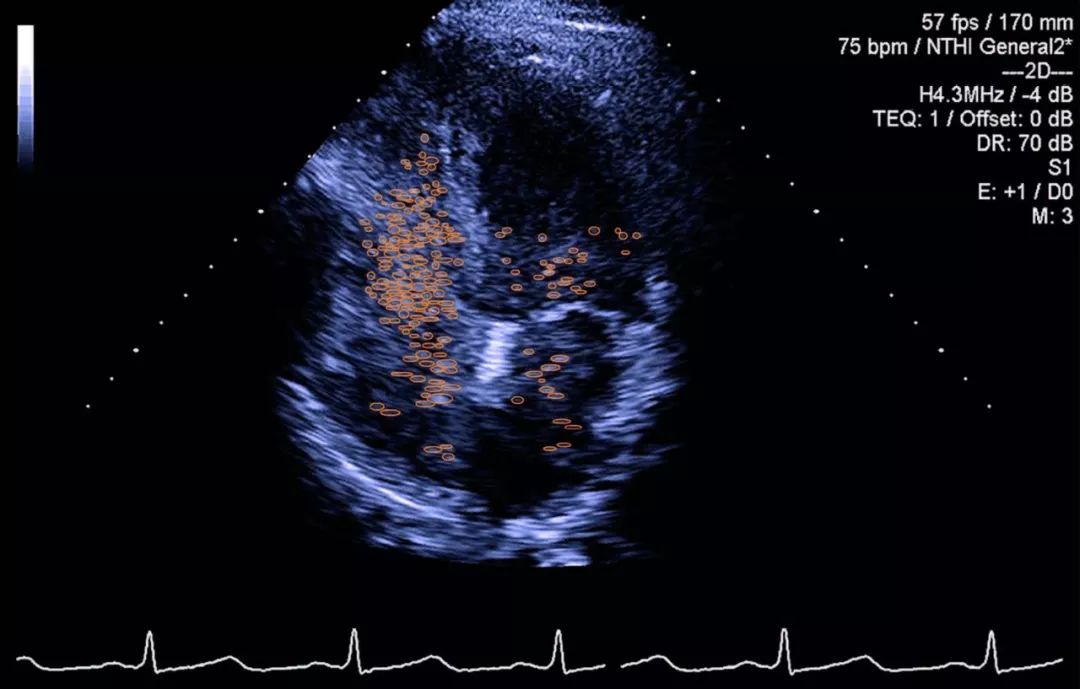

肝脏CT和超声显示肝硬化及门脉高压并侧支循环。为了确认诊断并进一步调查患者的病理生理学,进行了对比增强的经胸超声心动图,心脏左侧出现生理盐水气泡,表明肺内右至左分流(图)。

右心声学造影:采用手振生理盐水方法。具体配置方法为取两支10 ml注射器,一支抽取9 ml生理盐水和1 ml空气,通过三通开关将两支注射器相连,来回快速推注30次,使生理盐水和空气充分混合成含细小微泡的乳白色混合液,立即迅速推注。经食管右心声学造影选取能显示卵圆孔瓣的切面,经胸右心声学造影选取胸骨旁四腔心切面和心尖四腔心切面,观察valsalva动作后造影剂在心脏显影情况,造影过程中留存连续8~10个心动周期的动态图像。造影后逐帧回放并观察记录右心房充分显影后,进入左心房的微泡数量。为排除微气泡通过肺循环后回流入左心房形成的假阳性,选取前5个心动周期的结果,根据成像结果,选取微泡最多的切面评定分级。0级:0个气泡;1级:l~10个气泡;2级:11~30个气泡;3级:>30个气泡。